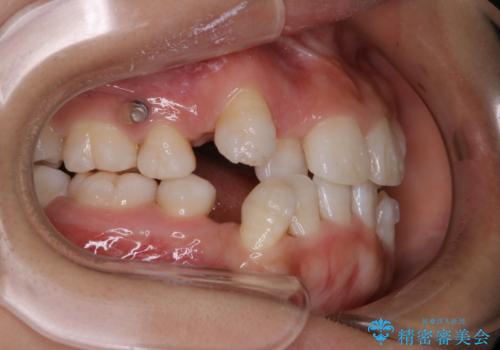

- インビザライン中に、コーヒーによる着色が気になるとのことでした。PMTC60分コースを行いました。

PMTC(保険外治療)は、毎日の歯磨きで落としきれない汚れや、コーヒ、紅茶・タバコのヤニなどの着色も除去します。目には見えない歯と歯の間・歯肉の境目・インビザライン中はアタッチメント周囲などに残っているプラーク(歯垢)もしっかり取り除きます。PMTCでは専門的な機械や材料を使用して、徹底的に汚れを除去するため、虫歯・歯周病・口臭予防などにつながります。